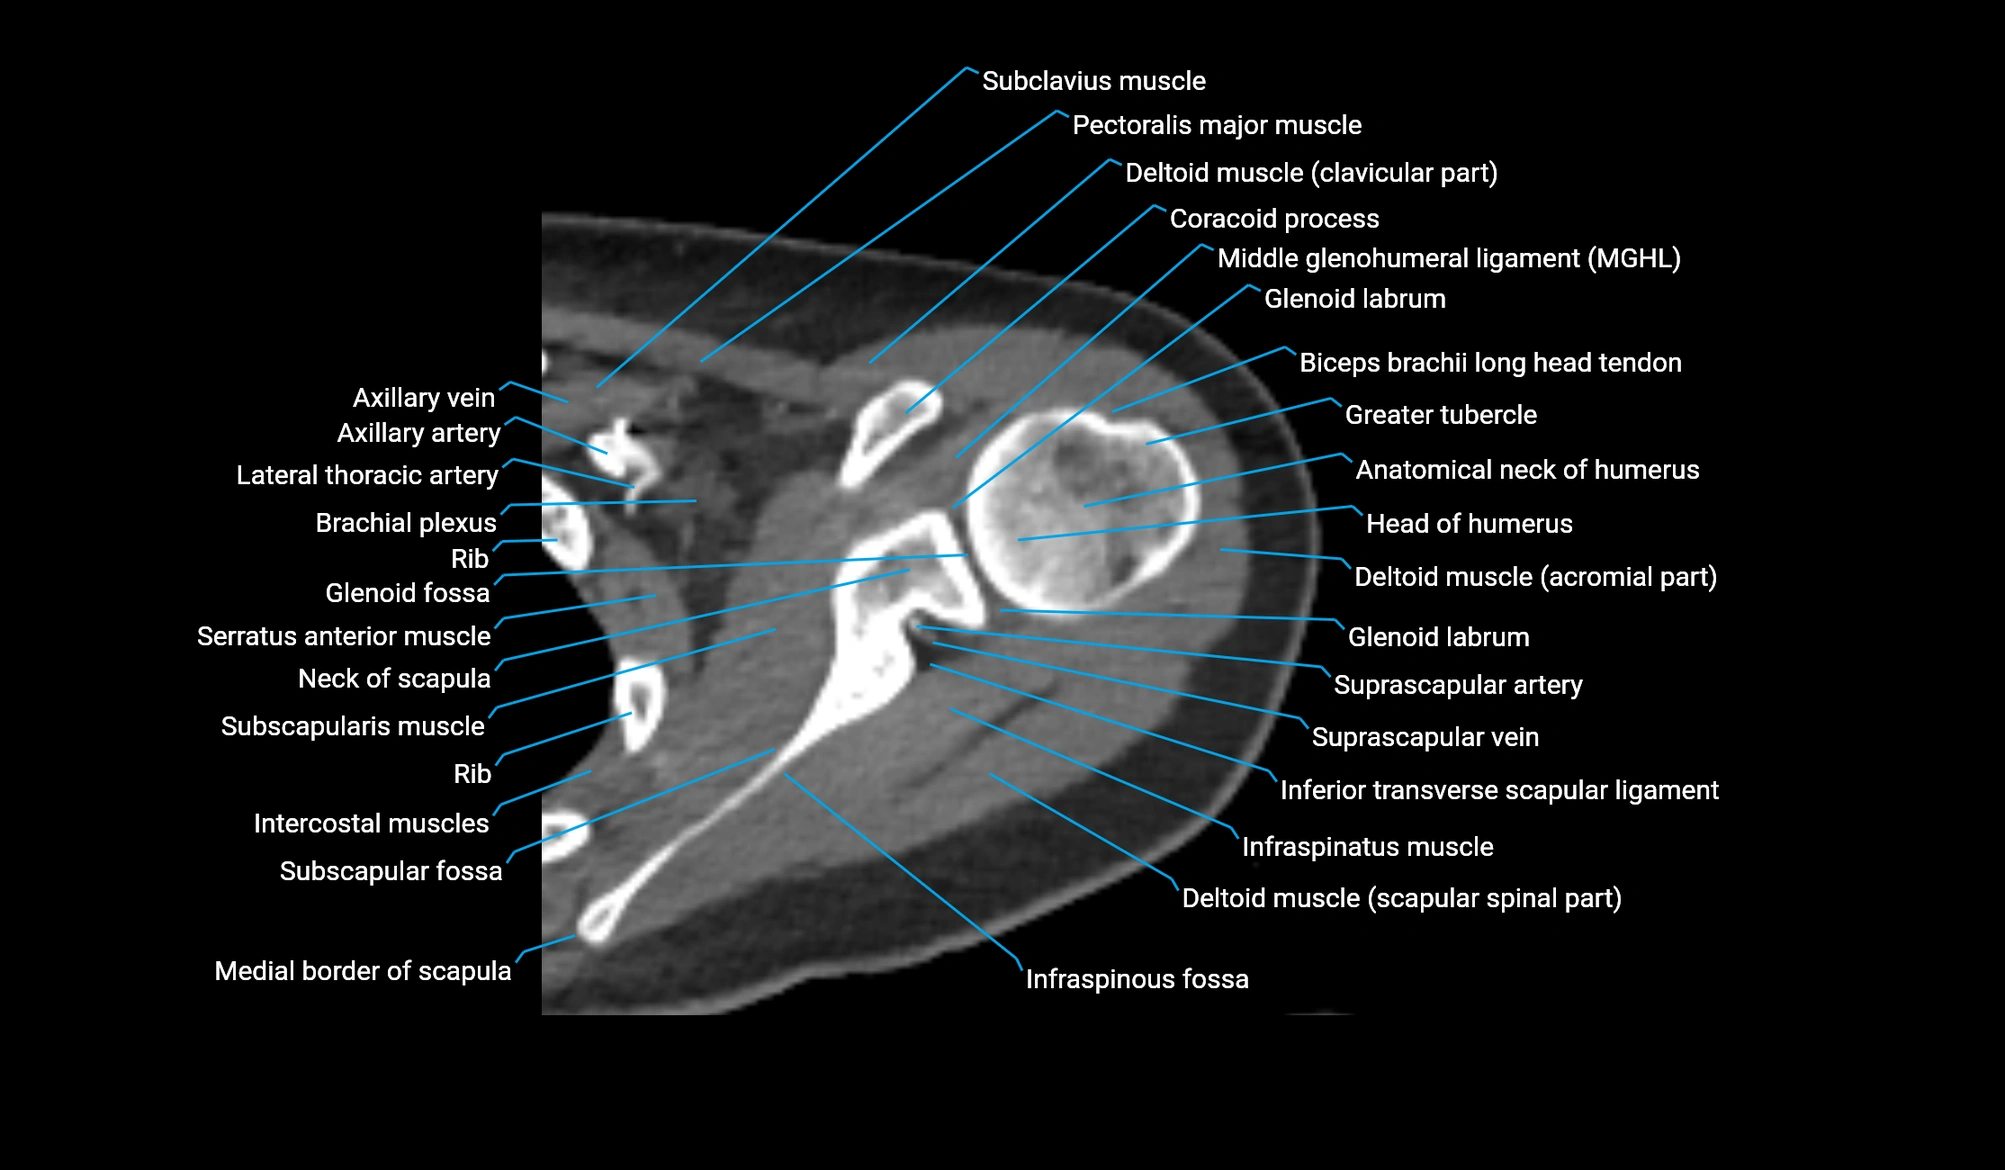

MRI image

CT image